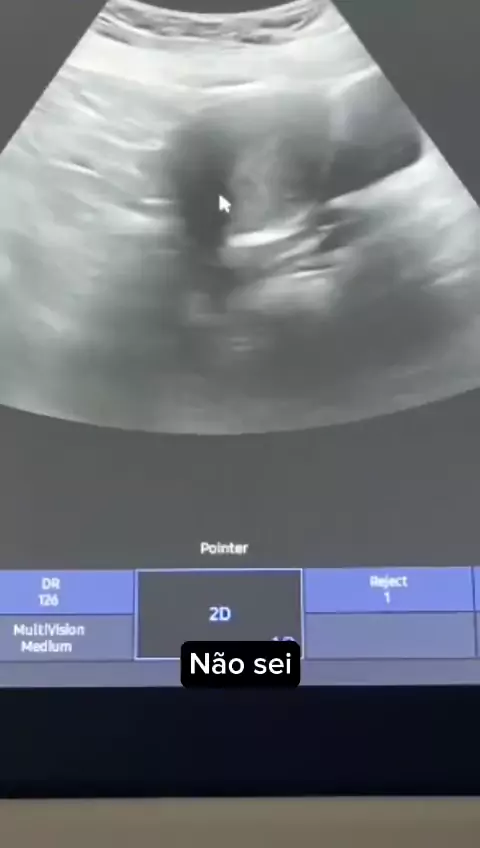

medicina vídeos

#medicine #medico #viraliza